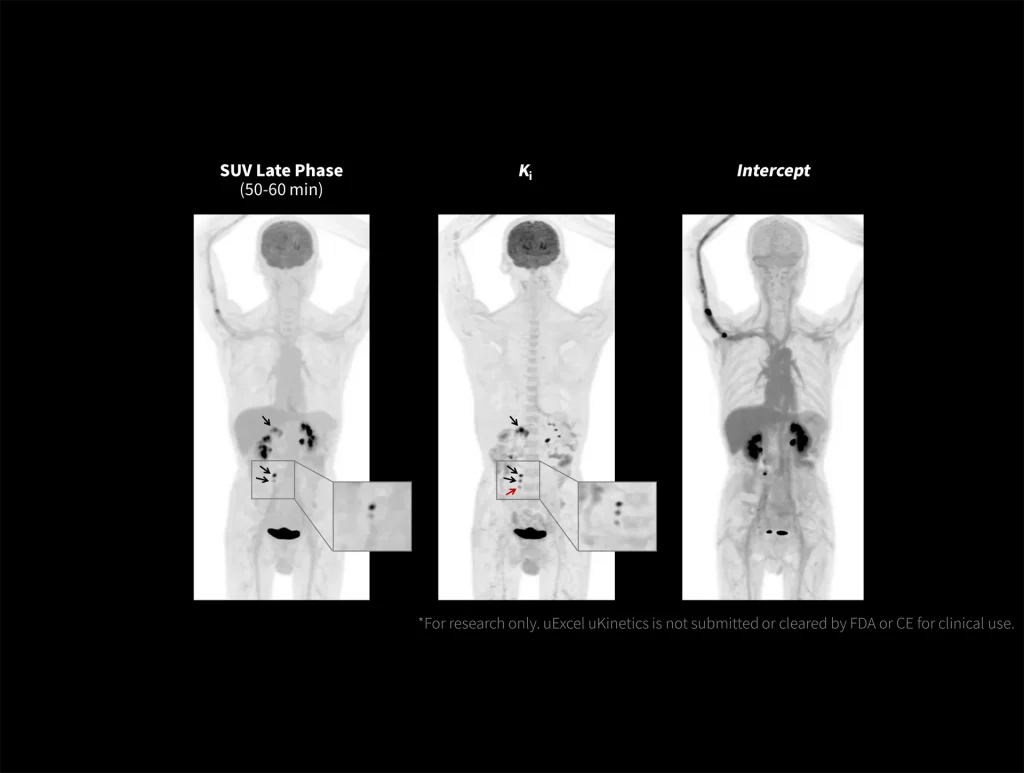

With the ultra-high system performance, uMI Panorama faces up to the challenges of tracers with different half lives and the complex scanning conditions, without compromise for image quality.

New-Tracer Imaging

Click on different tracers to see the images.